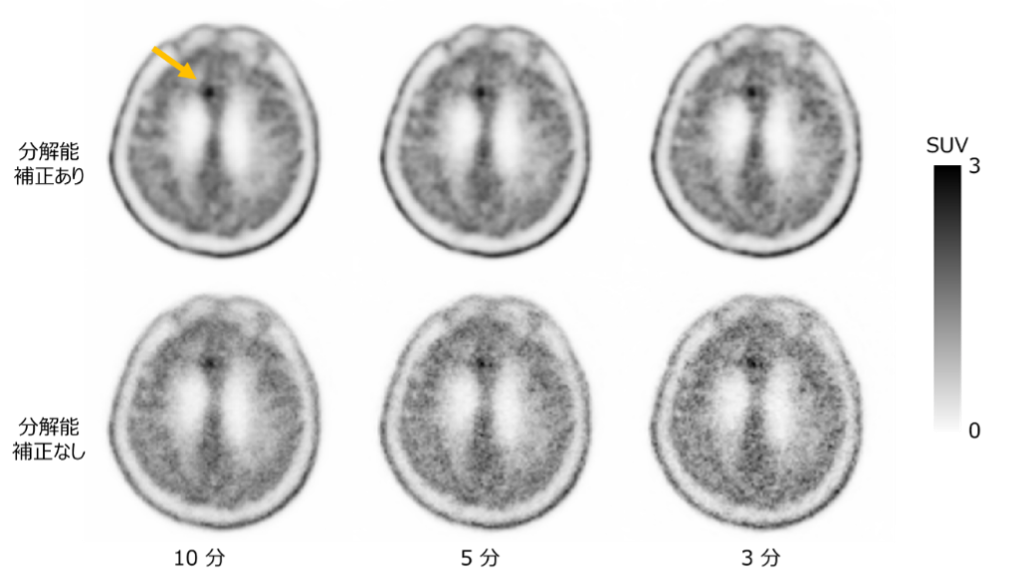

東北大学大学院医学系研究科放射線検査学分野の猪又 嵩斗(いのまた たかと)大学院生、千田 浩一(ちだ こういち)教授(災害放射線医学分野)らの研究グループは、ファントム5実験データおよび実際のメチオニンPET検査データから、3通りのスキャン時間(10分、5分、3分)に相当するデータを取り出しました。これらのデータを2通りの条件(分解能補正6あり・なし)で再構成し、1例あたり6通りの画像を取得しました(図1、2)。これらの画像のSUV評価および読影実験により、スキャン時間や分解能補正の有無による画質への影響を解析しました。その結果、3分スキャン、分解能補正ありの場合は、 10分スキャンとのSUVの誤差は5.2 ± 5.4%で、 放射線科医が全症例を「臨床応用可能な画質」と評価しました。また、3分スキャン、分解能補正なしの場合は、10分スキャンとの SUVの誤差は12.7 ± 8.5%でした(図3)。

3通りのスキャン時間に相当する臨床データを再構成して取得したPET画像(左からスキャン時間10分、5分、3分に相当)。分解能補正あり(上段)では分解能補正なし(下段)と比べて画像のざらつきが小さいことが分かる。